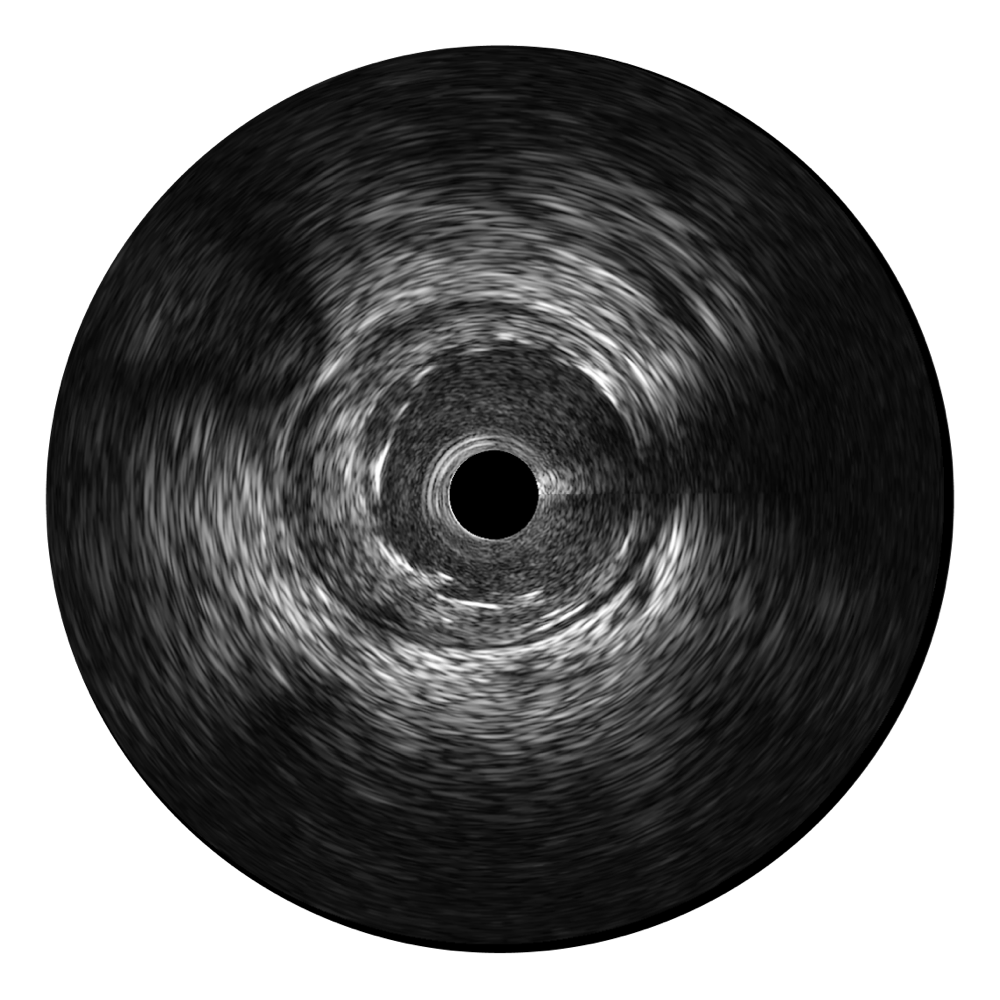

• 传统IVUS图像

对比传统IVUS导管成像,db真人体育官网宽频IVUS图像的近场支架梁显影更细腻,远场中膜外血管仍清晰可辨,兼顾远中近,兼顾分辨力与穿透深度